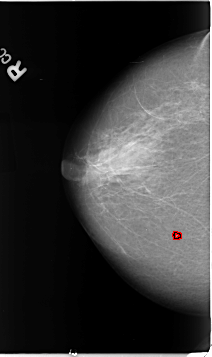

B_3098_1.RIGHT_MLO

RIGHT_MLO LINES 4648 PIXELS_PER_LINE 2624 BITS_PER_PIXEL 12 RESOLUTION 50 OVERLAY

FILE: B_3098_1.RIGHT_MLO.OVERLAY

TOTAL_ABNORMALITIES 1

ABNORMALITY 1

LESION_TYPE MASS SHAPE IRREGULAR MARGINS ILL_DEFINED

ASSESSMENT 4

SUBTLETY 3

PATHOLOGY BENIGN

TOTAL_OUTLINES 1

BOUNDARY